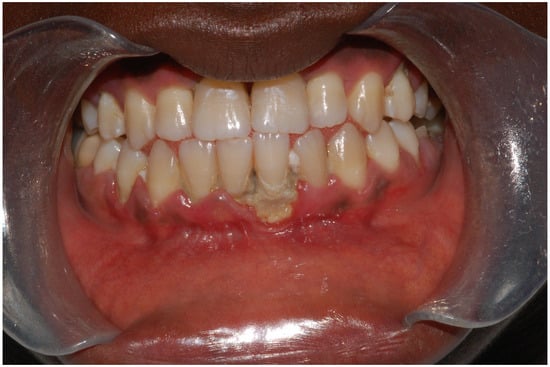

The significance of iron in periodontal health and the effects of anemia have been widely researched, with a particular focus on its general impact rather than on iron deficiency anemia (IDA) specifically, which has been less extensively covered. Research reveals a consistent association between chronic periodontitis and lower levels of Hb, HCT, and red blood cell (RBC) counts, highlighting studies spanning from 2009 to 2023 [65,66]. Moreover, data from the US National Health and Nutrition Examination Survey demonstrate a modest, yet statistically significant, increased risk of severe periodontal disease in individuals with insufficient iron intake, suggesting a parallel between the prevalence of IDA, caries, and periodontal diseases within certain populations. A notable case involves a 13-year-old male, a recent immigrant to the US from West Africa, a region prone to ID, who presented with gingival lesions indicative of acute necrotizing ulcerative gingivitis (ANUG). The patient was also infected with Aggregatibacter actinomycetemcomitans, a bacteria associated with aggressive periodontal disease (Figure 3).

Figure 3. Legends. Intraoral photograph of 13-year-old male showing a punched-out gingival lesion adjacent to the lower central incisors, resulting in a loss of the interdental papilla. Lesions such as these are a consequence of acute necrotizing ulcerative gingivitis (ANUG). This patient was a recent immigrant to the United States from West Africa, a region where iron deficiency is common. The patient’s oral cavity harbored Aggregatibacter actinomycetemcomitans, an organism associated with local aggressive periodontal disease.